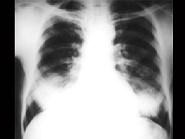

问题 女,34岁,新月体肾炎患者,最近咳嗽咯血,第一次行胸片检查考虑为双下肺感染,抗感染治疗后无明显好转,症状加重,4天后复查并行CT检查如图,应考虑为 ( )

选项 A.肺泡蛋白沉着症 B.肺含铁血黄素沉着症 C.双下肺肺炎 D.肺出血肾炎综合征 E.韦格肉芽肿

答案 D